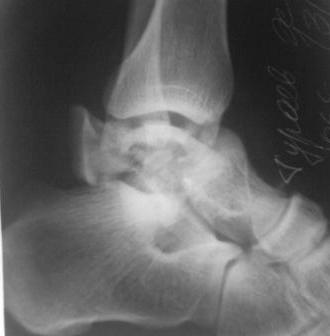

Re: Осколчатый перелом таранной кости

AT> Уважаемые коллеги, что делать?

Видимо, пытаться восстановить блок тарана с надеждой на сохранность функции суставов тут бесперспективно. Надо делать либо репозицию и артродез голеностопного и тарано-пяточного суставов, либо выкидывать отломки и делать берцово-пяточный блок.

Уважаемые коллеги, мне кажется, первой задачей в случаях, схожих с представленным, является профилактика глубоких некрозов мягких тканей, то есть спасение конечности как таковой. Тем более, в данном случае очевидным отягчающим прогноз фактором является предшествующее наложение гипсовой повязки. Для решения этой задачи, прежде всего, необходимо наложение аппарата внешней фиксации. Но не с целью мобилизации пациента, а с целью, прежде всего, устранения грубого смещения и вправления подтаранного вывиха. Далее аппарат должен работать как дистракционный и обеспечивать покой голеностопному суставу и стопе. Это позволит приступить к решению следующей задачи - лечению мягких тканей. Здесь - возвышенное положение конечности, покой в АВФ, улучшение реологии.

И только по улучшению состояния мягких тканей, при появлении морщин на коже стопы можно приступить к реализации третьей задачи - анатомичной репозиции (хотя бы основных фрагментов)и внутренней фиксации винтами с достижением мжфрагментарной компрессии и абсолютной стабильности. Надеюсь, у Вашего пациента дойдёт до этого дело, но, повторюсь, очень многое, если не всё в данной ситуации зависит от состояния мягких тканей.

Уважаемые коллеги! спасибо! Очень хочется сохранить сустав, но скорее всего не получится, мягкие ткани не важные. хотя отек и пузырки не нарастают, вроде стабилизируется, вчера во время вытяжения подтаранный вывых был устранен.